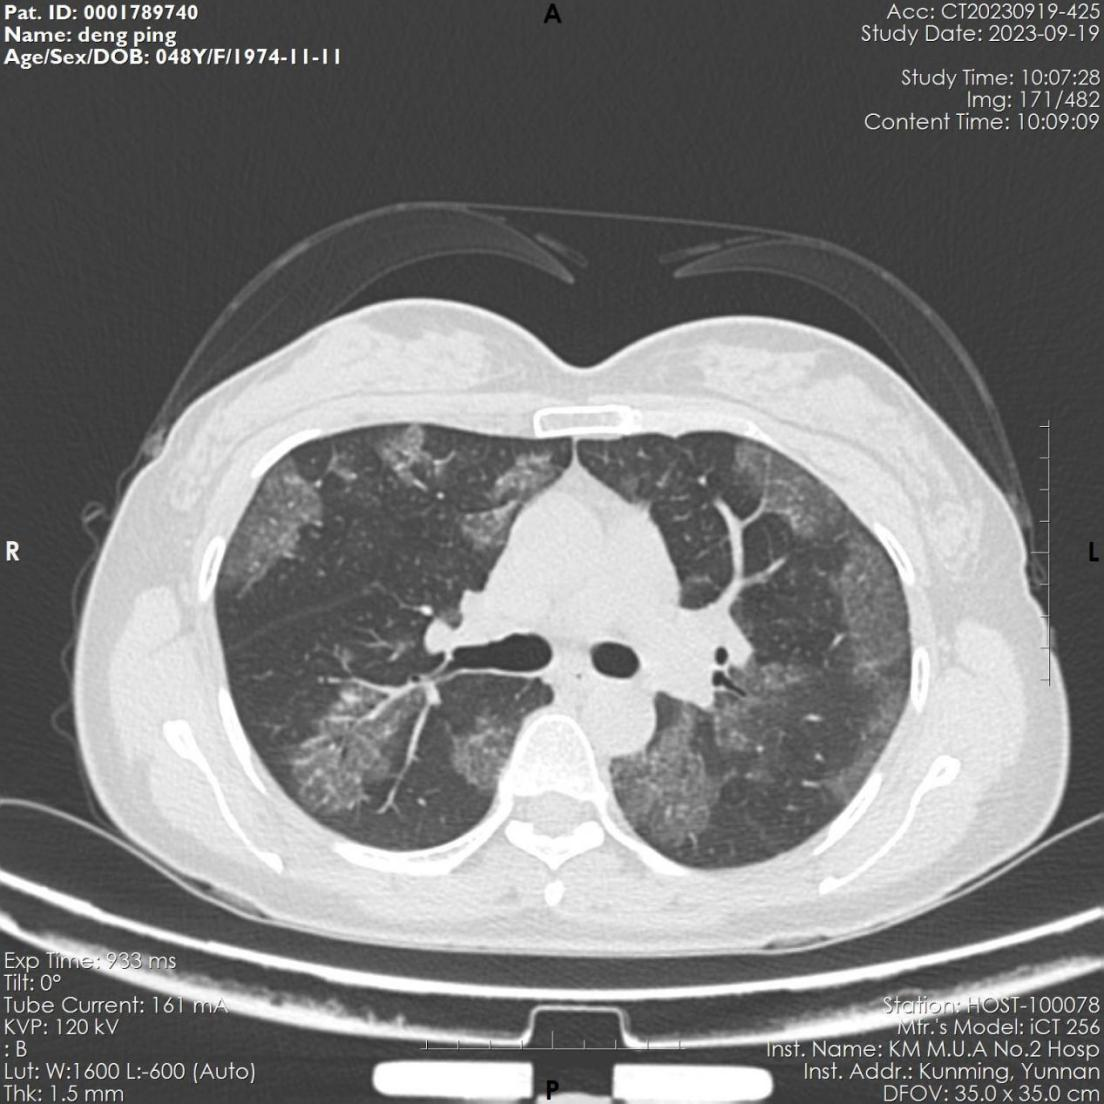

该患者,女,48岁,近3月来反复出现活动后胸闷气促。6月份因感染肺炎住院治疗,经抗病毒治疗后,咳嗽、咽痛等呼吸道症状缓解。9月因胸闷气促再发加重,来到财神捕鱼 全科医学科就诊,复查胸部CT显示肺部病变未见吸收,病变呈弥漫磨玻璃影,病变与正常组织分界较清,呈“地图征”,考虑“间质性肺疾病-肺泡蛋白沉积症可能”收住全科医学科。入院后完善电子支气管镜检查示双侧支气管未见明显异常,但各管腔内的肺泡灌洗液呈乳白色,肺泡灌洗液细胞学病理检查示肺泡巨噬细胞中间粉红色颗粒样物质,D-PAS和PAS染色阳性。结合病史、胸部CT、肺泡灌洗液呈乳白色、PAS染色阳性,该患者确诊罕见病“肺泡蛋白沉积症”。